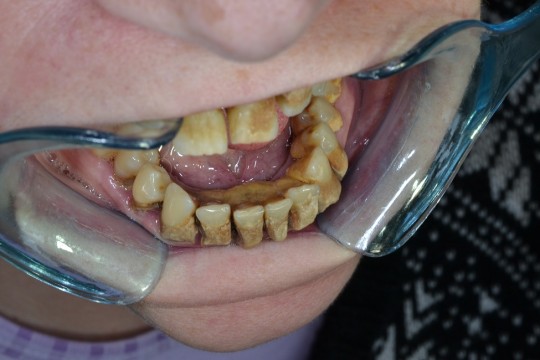

+

Fig. 3. Calculus

If the patient doesn´t brush and floss his teeth regularly, minerals from his saliva are deposited into the plaque film causing it to harden within 24 to 72 hours. It turns into tartar, also called dental calculus. The average time of formation the primary soft deposit to the mature mineralized stage takes about 12 days. It depends in individual tendency, roughness of the tooth surface, and personal care.

Unlike translucent plaque, the tartar is visible. It is not only aesthetically unpleasant, but even it can irritate the gums and lead to gingivitis. It is also very difficult to remove it. Plaque can be removed with proper brushing and flossing but patient has to go to see a dentist or dental hygienist to remove tartar, because calculus build-up on the teeth is strongly bonded to the enamel. Professional treatment of calculus includes scaling and polishing. DH uses scaler, curettes, and file, and other professional tools, e. g. air flow, ultrasound for treatment of prophylaxis. This treatment lasts around 30 minutes. The teeth are cleaned with air, or water or bicarbonate jet. This may be combined with ultrasonic staining for calculus which needs to be removed. Calculus should be professionally removed twice a year.